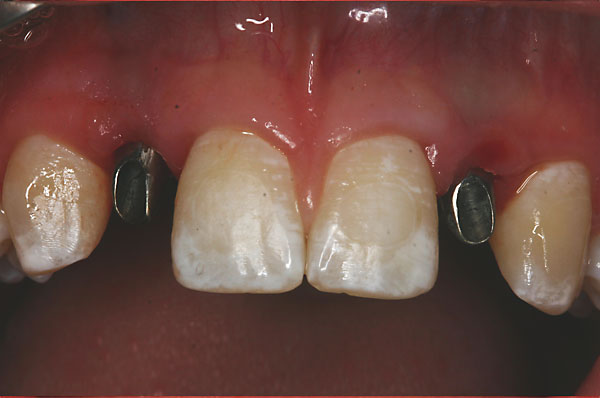

Fall: Von der Prothese zur fixen Krone

7 |

8 |

9 |

|

10 |

11 |

12 |